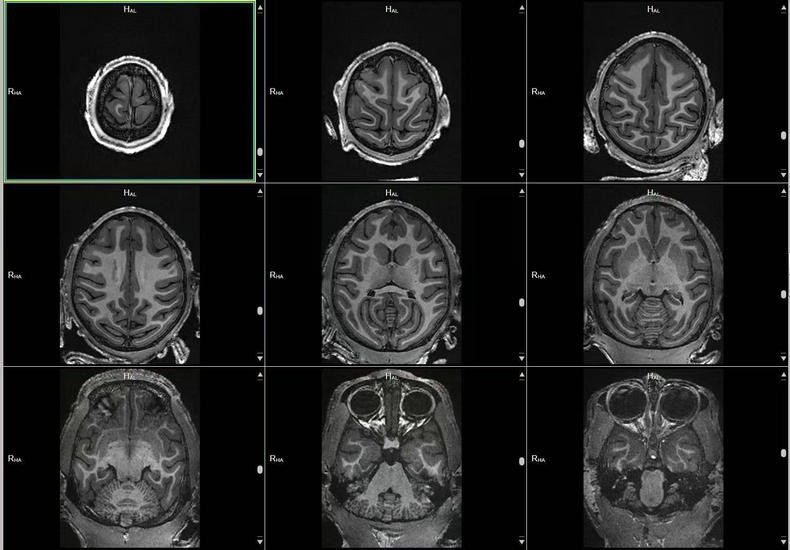

预定本数据集为2023-2025年对131只4-12岁青年健康雄性猕猴的脑部磁共振扫描收集的数据,主要包括T1w序列和T2w序列影像(3D影像),对于神经学、心理学、行为学等多个相关学科的研究提供丰富的脑数据支撑。

a.物种:猕猴

b.实验动物信息

样本数量:131只

年龄分布:4-12岁

重量分布:3-17kg

性别分布:雄性131只

c.扫描仪规格

扫描仪类型:联影uMRNX 3.0T磁共振扫描仪器

线圈:12通道猕猴专用头线圈